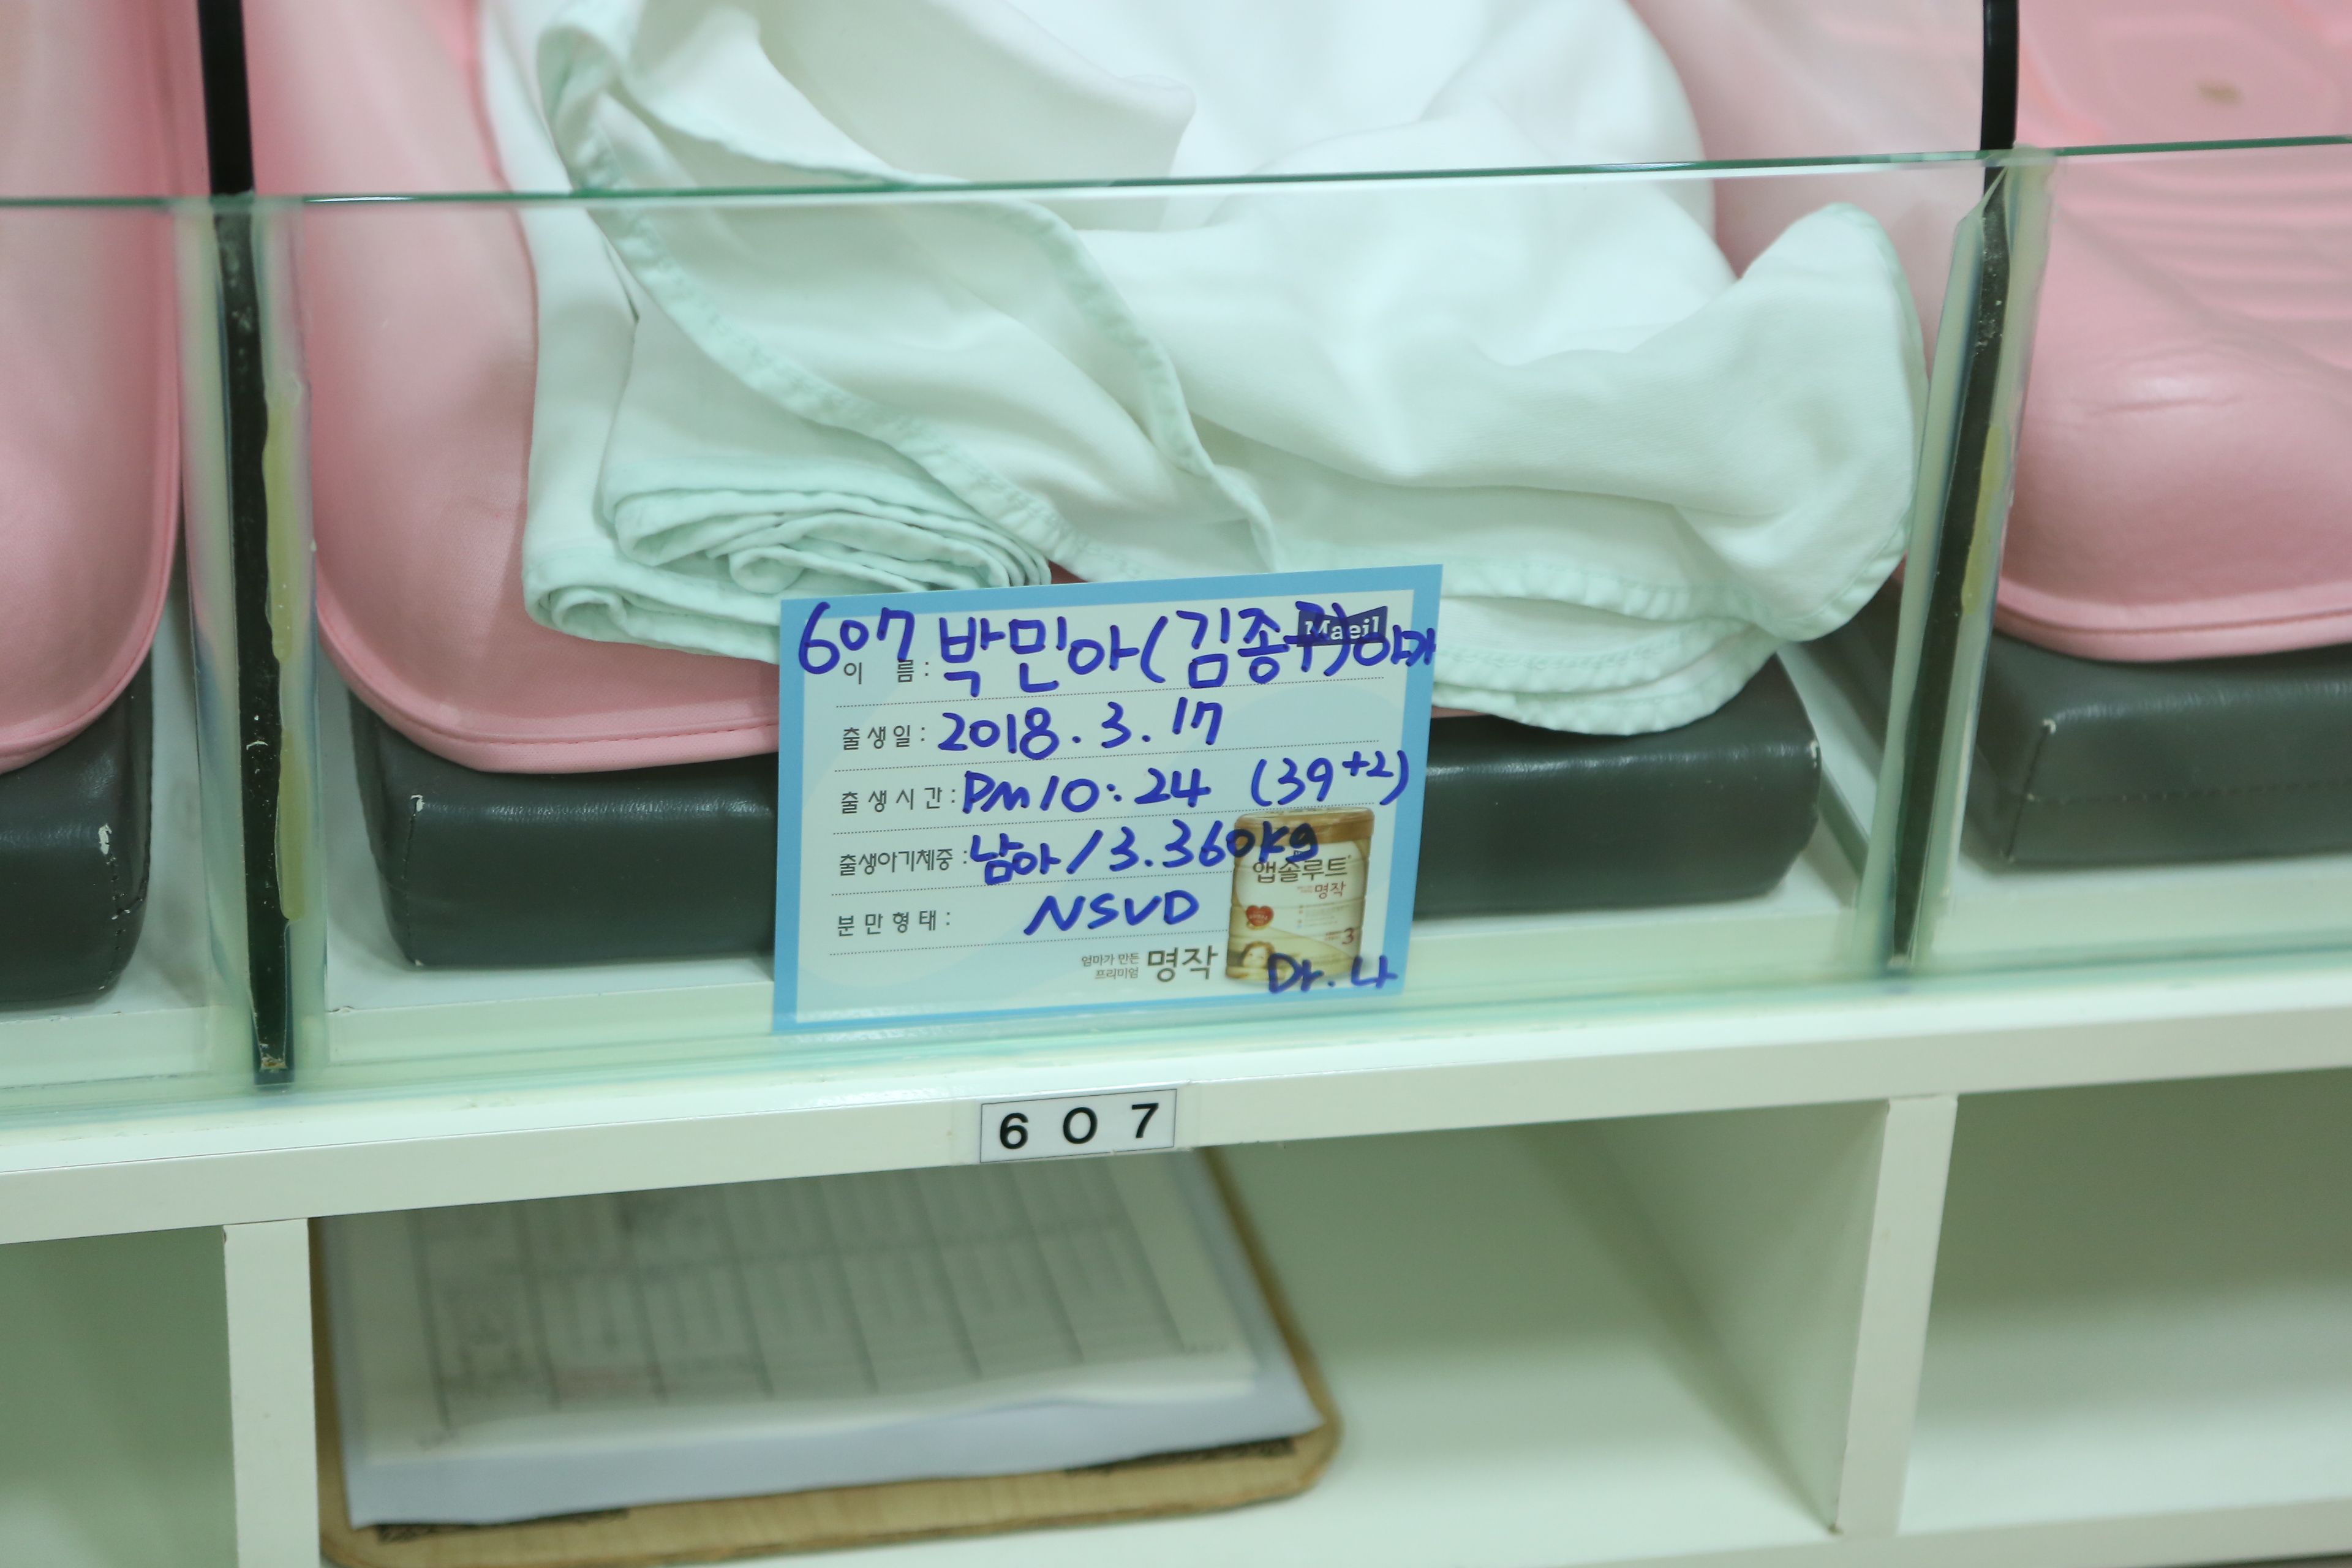

2018년 4월 27일 신생아실과 산후조리원의 예성이 본문